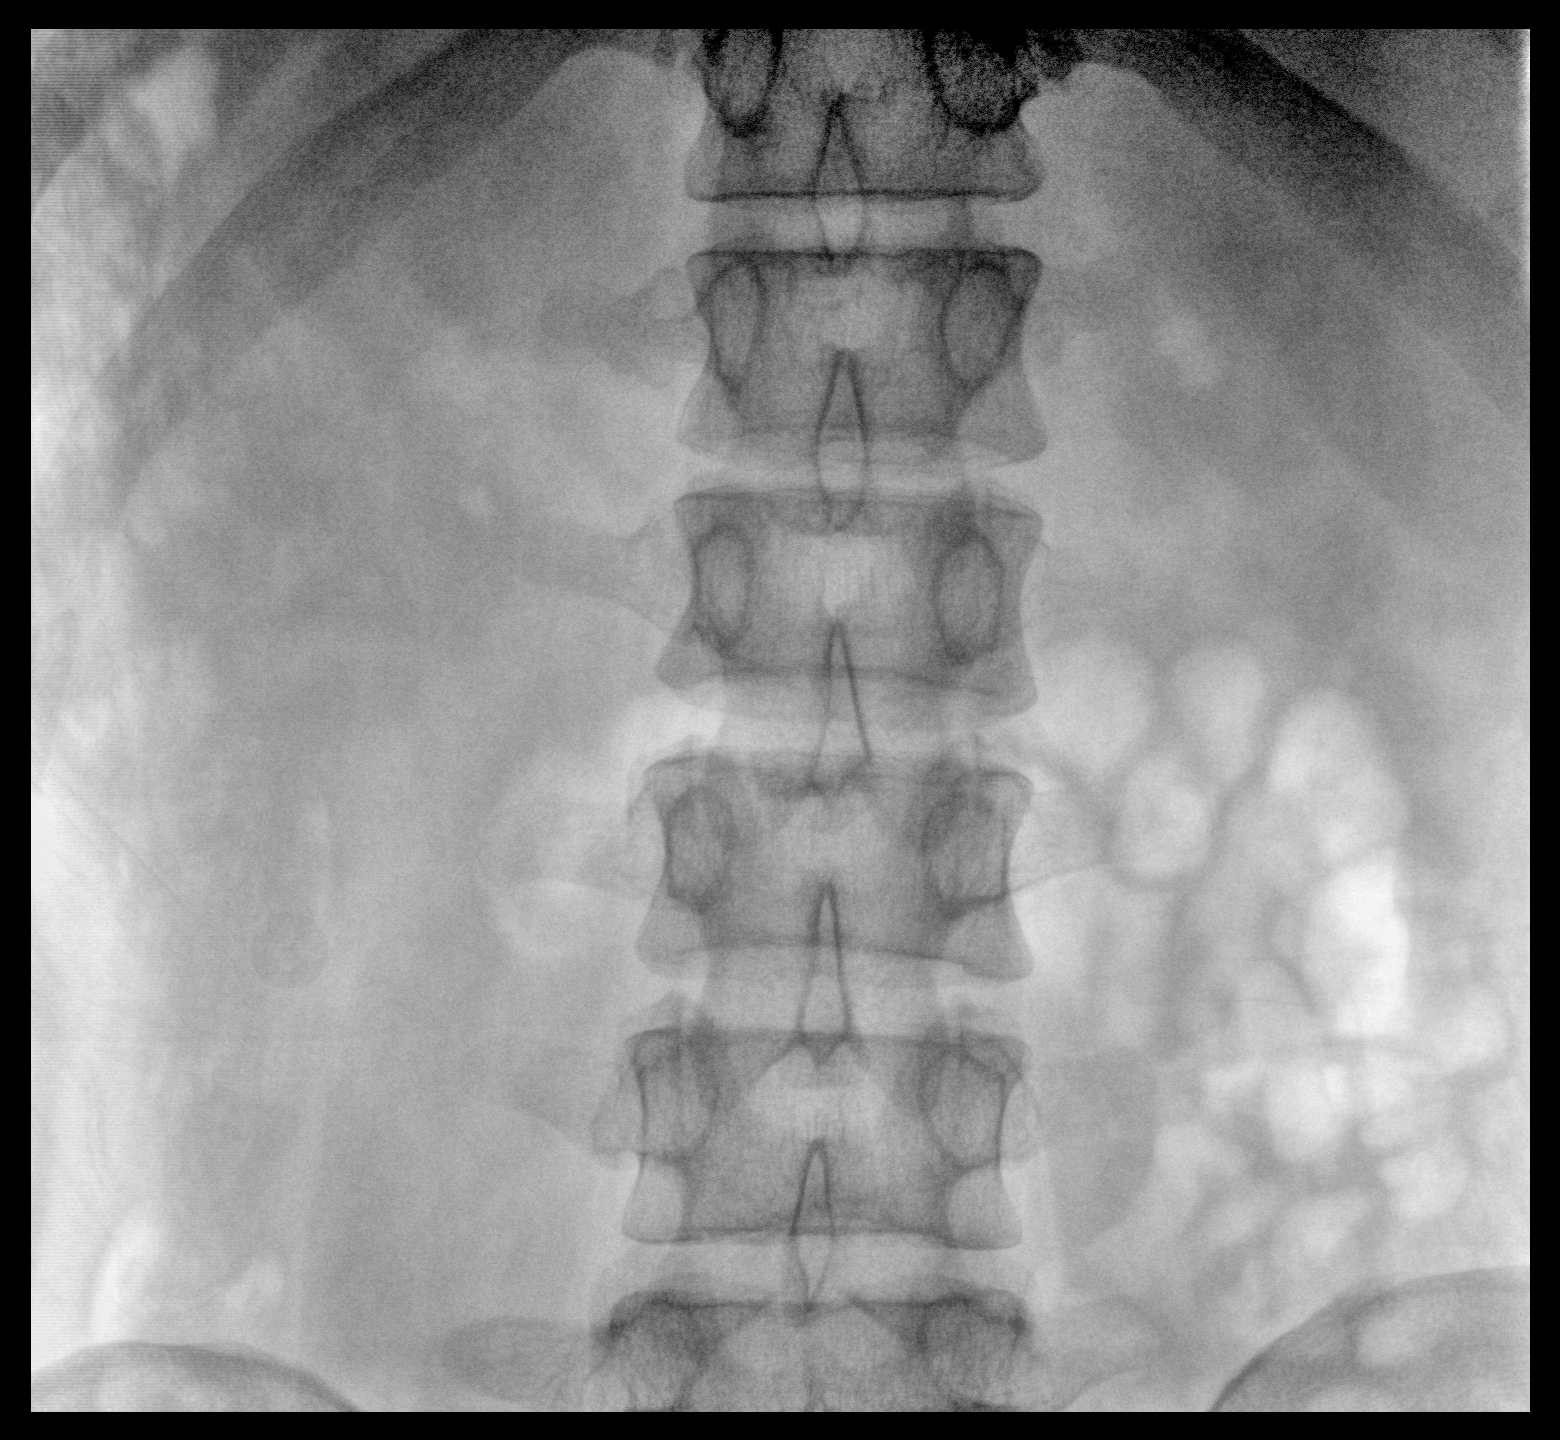

臨床適用科室:骨科、普通外科、矯形外科、創(chuàng)傷外科、泌尿外科、脊柱外科、疼痛外科、消化科、婦科等科室。

大尺寸動(dòng)態(tài)平板探測(cè)器,高DQE、低噪聲、圖像清晰。采用多分辨率圖像增強(qiáng)處理技術(shù),不同部位不同圖像處理算法,滿足客戶多樣化的需求。

采用智能變頻脈沖透視技術(shù),優(yōu)化圖像質(zhì)量的同時(shí)降低輻射劑量,呵護(hù)醫(yī)患健康